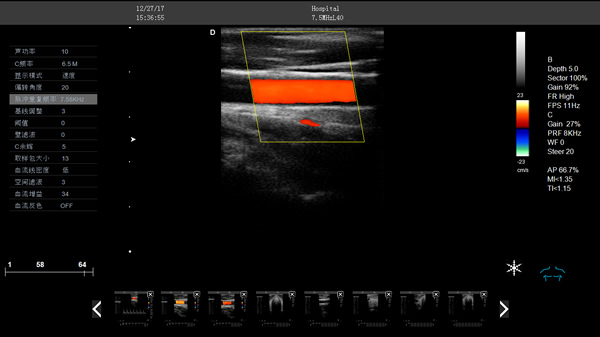

DW-CT580 全數(shù)字彩色多普勒超聲診斷儀

DW-CT580,全數(shù)字彩色多普勒超聲診斷儀,推車式彩超